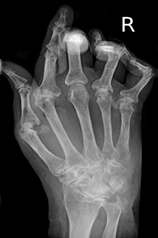

Con il passare del tempo, l’artrite reumatoide, può creare lesioni alle strutture circostanti come tendini o legamenti, o sviluppare erosioni delle ossa con possibili deformazioni.

| Le prime articolazioni ad essere colpite maggiormente sono | Le articolazioni sottoposte a grandi carichi come le anche, le ginocchia, le dita delle mani e dei piedi ed infine ma non ultime le vertebre. Può essere colpita anche una singola articolazione. | Le piccole articolazioni come nelle mani, nei piedi, o nei polsi ad esempio. Sono colpite multiple articolazioni sia nel lato destro che sinistro. La presenza in entrambi i lati è spesso molto indicativa. |

La radiografia non è l’esame più utilizzato ai primi stadi poiché non mostrerebbe nulla. Potrebbe essere utile, insieme alla risonanza magnetica nelle fasi più avanzate, qualora l’artrite reumatoide causi danni come erosioni delle ossa o lesioni ai tendini e legamenti che costituiscono l’articolazione.